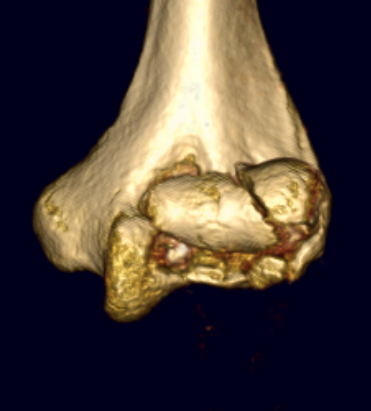

Dubberly Classification

Type I Type Ii Type III

Capitellar fracture

Capitellum + trochlea fracture

In one piece

Double arc sign seen on xray

Capitellum + trochlea fractures

In two separate pieces

Double arc sign on xray